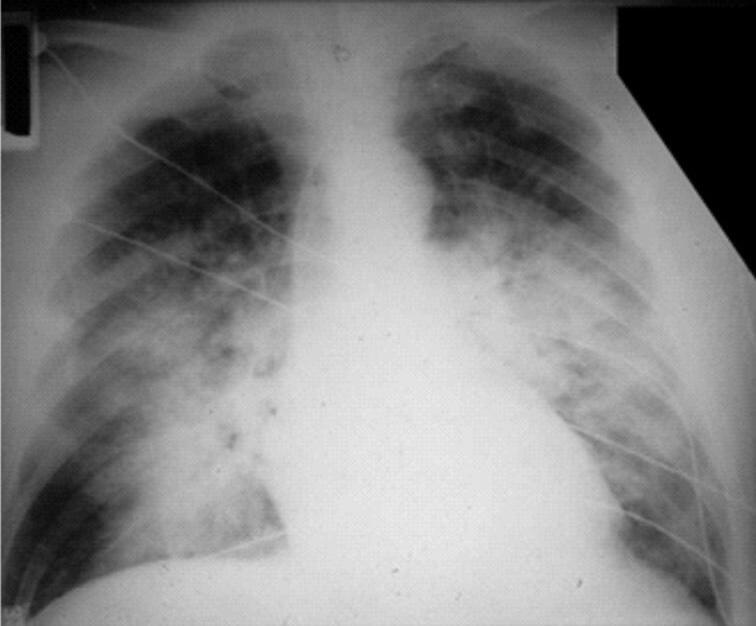

28 Síndrome da Angústia Respiratória Aguda – Posição Prona e Oxigenação por Membrana Extracorporal, 251

Alexandre Marini Isola  Diogo Toledo  Flávia J. A. Pfeilsticker